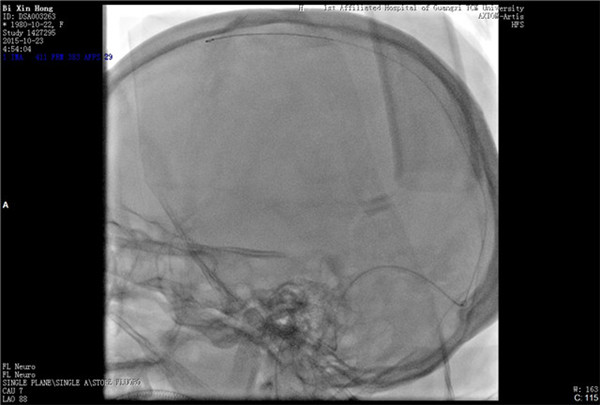

经与患者及家属充分沟通并获得同意后,外六科脑血管病介入治疗团队立即为患者行全脑血管造影,造影结果证实上矢状窦血栓形成,整个上矢状窦完全闭塞,若不采取措施病情很快就会恶化。再次征得家属同意后果断采取微导管介入手术治疗,手术在起病后当晚开始,由于患者血栓位置深在,需要经动、静脉双重途径置管,技术难度较大。术者选取Solitaire支架( 美国 公司)置入微导管远端,释放支架并在原位作短暂停留使支架与血栓充分接触并黏附,一起回撤支架与微导管取出血栓,手术一直持续到第二天凌晨。术后留置导管一条,用于每天以药物继续溶栓。术后患者即清醒,头痛明显缓解,无神经功能缺失。手术第二周时患者已经能够生活自理。2015年12月12日患者痊愈出院。

微导管置入上矢状窦

支架取出血栓